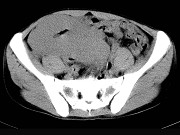

- 单项选择题男,23岁, 下腹部肿块伴持续性钝痛1月余,影像所见如图, 最可能的诊断为 ( )

A、小肠癌

B、小肠淋巴瘤

C、小肠转移瘤

D、小肠结核

E、小肠间质瘤